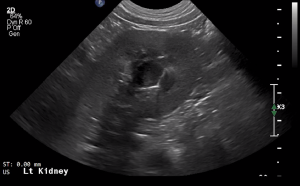

SIMON Ultrasound Database

This ultrasound database is a free resource for students and doctors!

Our collection includes videos of dogs, cats, horses, cows, humans, and many other species!

–Canine and Feline abdominal ultrasound videos were generously provided by the Cummings School of Veterinary Medicine at Tufts University.